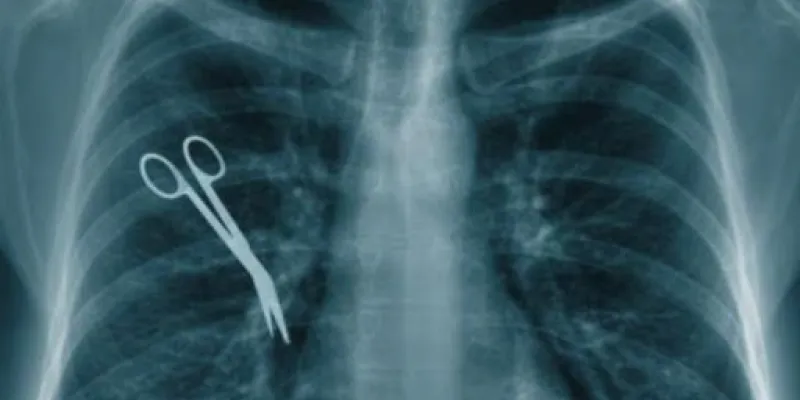

Quelques cas d’erreurs médicales

De son côté, maître Gaston Watou, avocat au barreau du Cameroun, n’en revient toujours pas de la mésaventure d’un de ses clients il y a quelques années à l’hôpital général de Douala où ce dernier était arrivé pour être pris en charge.

Au cours de l’administration des soins, un mauvais usage du cathéter lui avait causé une thrombose veineuse profonde. Il s’agit d’une maladie qui se caractérise par la formation de caillots de sang dans la veine.

« Par la suite, le patient était mort des conséquences de cette mauvaise utilisation du cathéter. De pesanteur en pesanteur, la procédure que nous avions engagée n’a jamais pu aboutir », regrette encore aujourd’hui l’avocat.